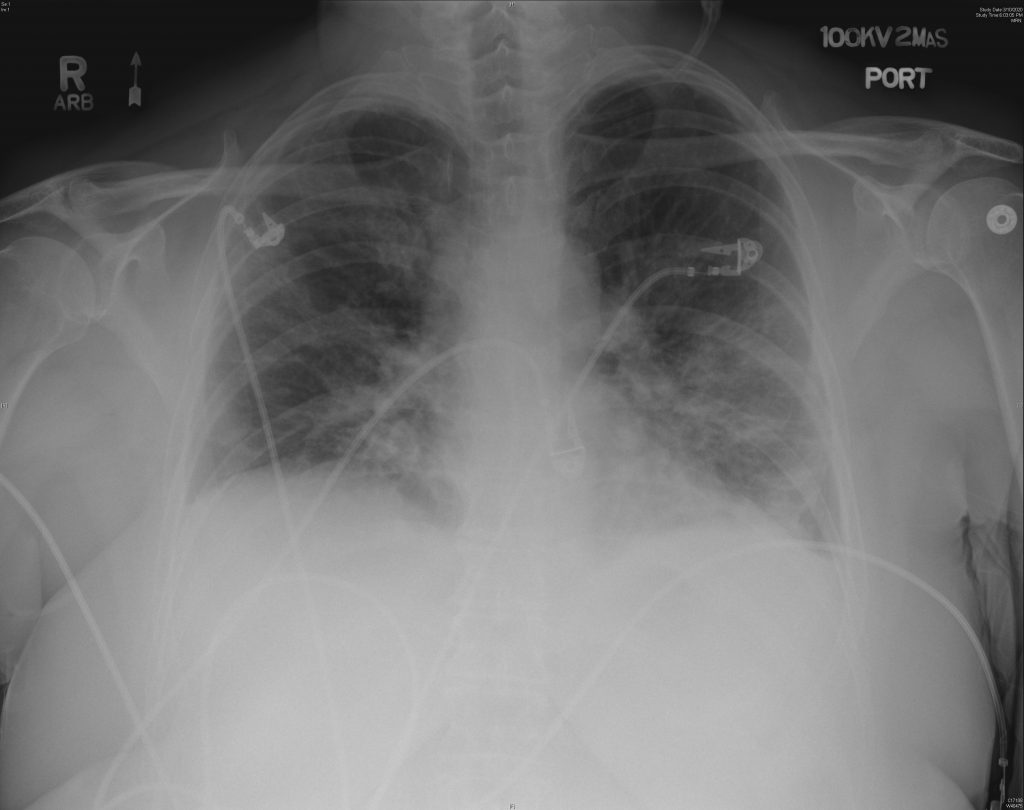

A new study published in the Canadian Medical Association Journal (CMAJ) examined ultrasound images taken from the lungs of a 64-year-old woman diagnosed with COVID-19, revealing how the virus can present itself in the lungs.

Credit: CMAJ. CMAJ

The ultrasound shows “pleural thickening, subpleural consolidation (also known as ‘skip lesion’) and multifocal B-lines,” researchers said.

“These images show changes in the lung that occur due to the SARS-CoV-2 virus (which is responsible for COVID-19) infecting the lungs, and the body’s subsequent immune response to the infection,” said Dr. Anish Mitra, a critical care physician in Surrey, B.C.

“These ultrasound images indicate that there is inflammation in the lungs due to the infection.”

According to Mitra, ultrasound images such as these can help to guide treatment in patients with severe cases of COVID-19.

However, ultrasound should not be relied on during the diagnosis stage because inflammation — similar to what is shown in these images — can be seen in other viral pneumonias, including influenza.

“Rather, physicians can use lung ultrasound findings to help them make a diagnosis of COVID-19 or other diseases in the right clinical context,” Mitra said.

Credit: CMAJ. Credit: CMAJ